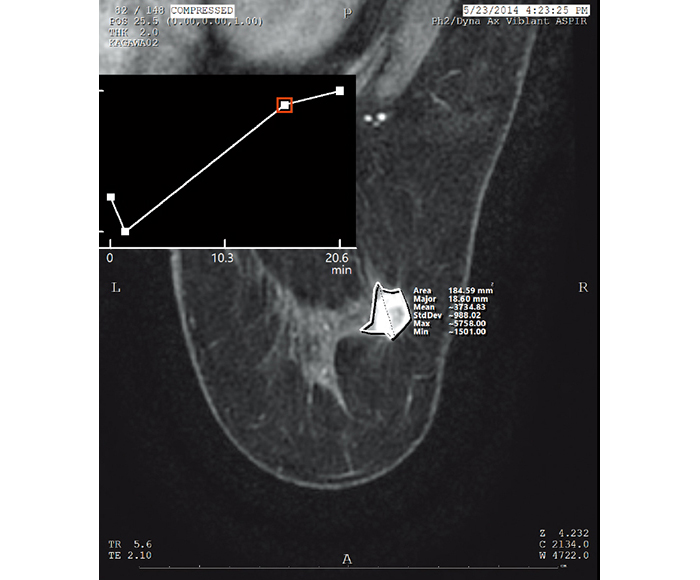

Los valores para la medición de ROI y rayos X pueden obtenerse a partir de la información de cada modalidad de imagen.

![[image] Radiografías de la curva de intensidad temporal](https://asset.fujifilm.com/www/mx/files/2025-07/22314a4bb2fae90b74293188ad1783b4/pic_amulet-bellus-2_06.jpg)

Curva de intensidad temporal